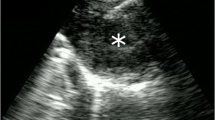

Pathologic Diagnosis

The cytology smear and cell block show malignant cells (Fig. 7.7); immunostains performed on the cell block sections reveal the malignant cells are positive for TTF1 and napsin, consistent with metastatic adenocarcinoma from lung primary.

FISH Analysis

-

POSITIVE for variant ALK1 gene rearrangement with loss of 5′ ALK in 81% of the 200 cells scored (Fig. 7.8)

Fluorescence in situ hybridization (FISH) of ALK1 rearrangement. Dual-color break-apart probes show 1 fusion (red + green/yellow, the red part is smaller in many cells) and 1–2 red signals, indicating loss of 5′ (green) signal. Although rearrangement typically shows split of green and red signals, loss of 5′ green signal is a variant pattern indicating rearranged ALK1 gene

Discussion

Although ALK1 rearrangements are present only infrequently in NSCLC, they are targetable alterations required to be tested per current practice guidelines. FISH is a sensitive and specific method to detect ALK rearrangements (and other rearrangements such as ROS1 and RET). To cover variable partners of ALK1 fusion, a break apart-probe design is preferred in the clinical FISH laboratory because the specific partner does not affect the therapy response. In the fusion protein, only the ALK kinase portion is functionally relevant; therefore a variant rearrangement with loss of 5′ signal and retention of the 3′ kinase portion, like in this case, is considered positive for ALK1 fusion.

EML4 is the most common gene partner of ALK1; both genes are located in the short (p) arm of chromosome 2. Segment inversion of chromosome 2p results in the constitutively active ALK-EML4 fusion protein. AlK1 can also fuse with other genes, such as TFG, KIF5B, KLC1, etc. In this case, an ALK-EML4 fusion gene has been confirmed in a later liquid biopsy test.